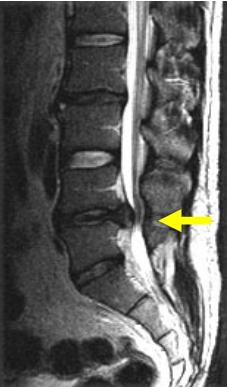

왼쪽 사진의 경우 디스크 환자의 사진입니다. 보통 디스크 환자의 경우 허리뼈 1-3(4) 번은 일자로 서 있고 허리뼈4-5번(엉치뼈)가 과도하게 꺾여있습니다.